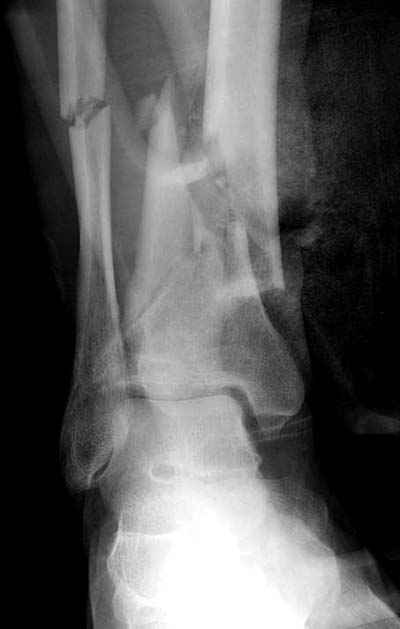

Разбор тактики лечения низких переломов костей голени становится популярной темой. Споры не только по тактике "по данным некоторых зарубежных авторов, при переломе обеих костей голени на одном уровне рекомендуется фиксация обеих", а также по импланту (гвоздь или пластина) и по локализациям имплантов "укладывать на заднюю поверхность при низких переломах"

Во всех описанных случаях единственное, что объединяет, это локализация перелома, а так это  различные по механизму травмы. Различные импланты, и хирургическая техника отличается друг от друга. Разные по возрасту и по активности больные. Поэтому из-за невозможности создать единый алгоритм "до сих пор идет дискуссия".

Возвращаясь к разбору "БИОС у пожилого пациента", тогда многие из наших коллег проголосовали за то, чтобы оставить на одном интрамедуллярном гвозде. На рентгене плохое качество кости (остеопороз), костные фрагменты в середине канала, и на малоберцовой имеются фрагменты по линии перелома. В таких случаях гвоздь идеальный фиксатор, потому что создается равномерная компрессия на обе кости. А латеральная фиксация на малоберцовой, как распорка, повела бы в варус.

Данная фиксация пластинами сделана классическим АО методом описанным еще в 1989 году в книге J. Mast и R. Ganz “Planning and Reduction Technique in Fracture Surgery”. В то время antiglade method DCP пластиной в 4.5 мм c повторением натурального изгиба голени в н/3 считался одним из оригинальных. Повторение оригинальной концепции и фиксация спонгиозными шурупами в дистальном отделе доказывает, что коллеги хорошо освоили метод АО. Но для уменьшения раздражения пластиной изнутри в нижнем отделе, авторы применяли технику погружения пластины в кортекс. Профилактические меры не всегда помогали, и в неумелых руках "передне-медиальный АО доступ" часто осложнялся кожными осложнениями.

Без современных материалов создать хорошую фиксацию становится трудной задачей, и этот случай характерен тем, что достигнутую идеальную репозицию испортили старомодной техникой. Исследования показали, что спонгиозные шурупы в метафизарных частях не создают механические преимущества как считали раньше. Кортикальные винты менее агрессивны и не оставляют дефекта кости после их удаления.